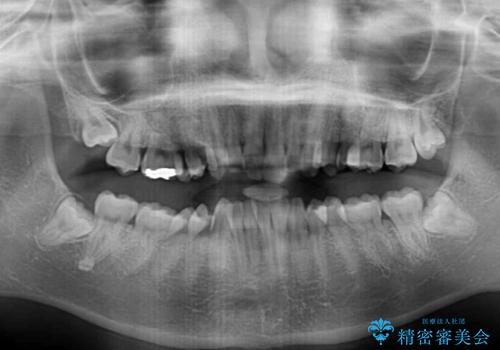

- 全体的な歯列の叢生を気にして来院された患者様です。

奥歯の咬み合わせを見ると、片方は上顎が下顎に対して相対的に前方にあり、他方は交叉した咬合の状態でした。

咬み合わせを改善するためには、上顎臼歯を後方に移動させた咬み合わせにする必要があります。

インビザライン単体で改善することも可能ですが、ディープバイトのためインビザライン単体で達成する可能性が低いと考えられたため、カリエール・ディスタライザーという補助装置を併用して、より確実性を上げることとしました。